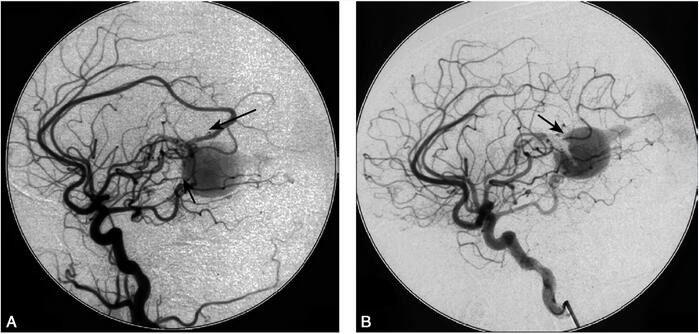

1小时条评论1 病例简介 患儿女,7岁,因左侧肢体无力伴头痛、头晕3日,突然加重1日于2009年3月27日坐轮椅入院。患儿于2009年3月23日前开始出现左侧肢体无力,行走不稳,伴间断头痛、头晕,在当地医院颅脑CT平扫和增强提示...